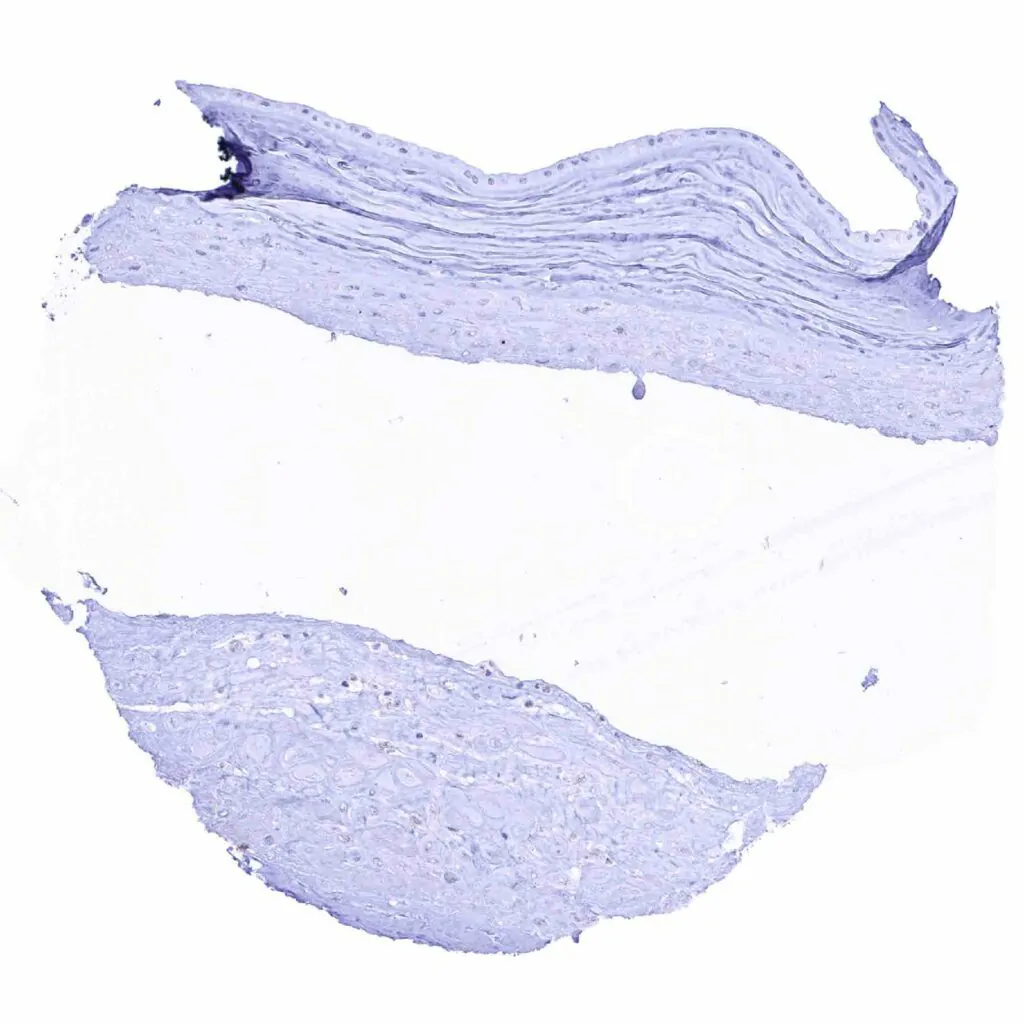

Aorta, media